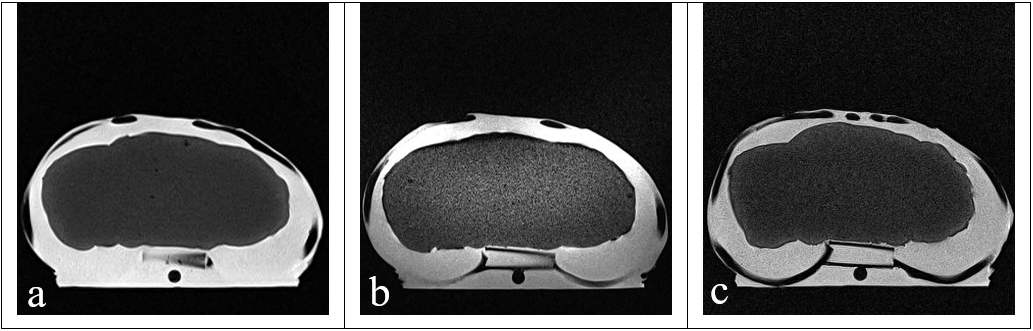

Figure 2: Axial MR images of the phantom (a) PD weighted (b) T1 weighted (c) T2 weighted